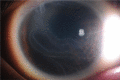

Primary congenital glaucoma (PCG) is a rare disease affecting children early in life. PCG was considered untreatable with inevitable blindness. However, recent advances in biochemical and genetic studies, the introduction of new diagnostic tools, intraocular pressure (IOP) lowering medications and improvement of surgical techniques have led to a better understanding of this devastating disease and preserving the vision of affected children. This paper presents an updated and broad overview of PCG in terms of the epidemiology and genetic aspects, particularly in Saudi Arabia, the clinical presentation and diagnostic approach to PCG with major emphasis on the treatment options.